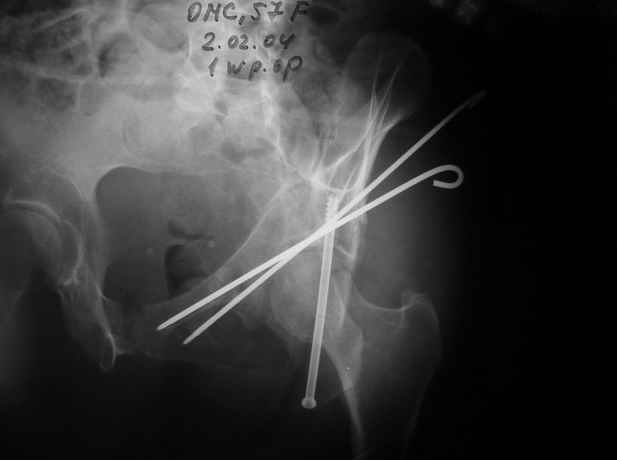

Еще раз спасибо за комментарии и готовность помочь с имплантами. Постоп картинки в приложении,

27.01.04

02.02.04

10.02.04

12.04.04

02.06.04